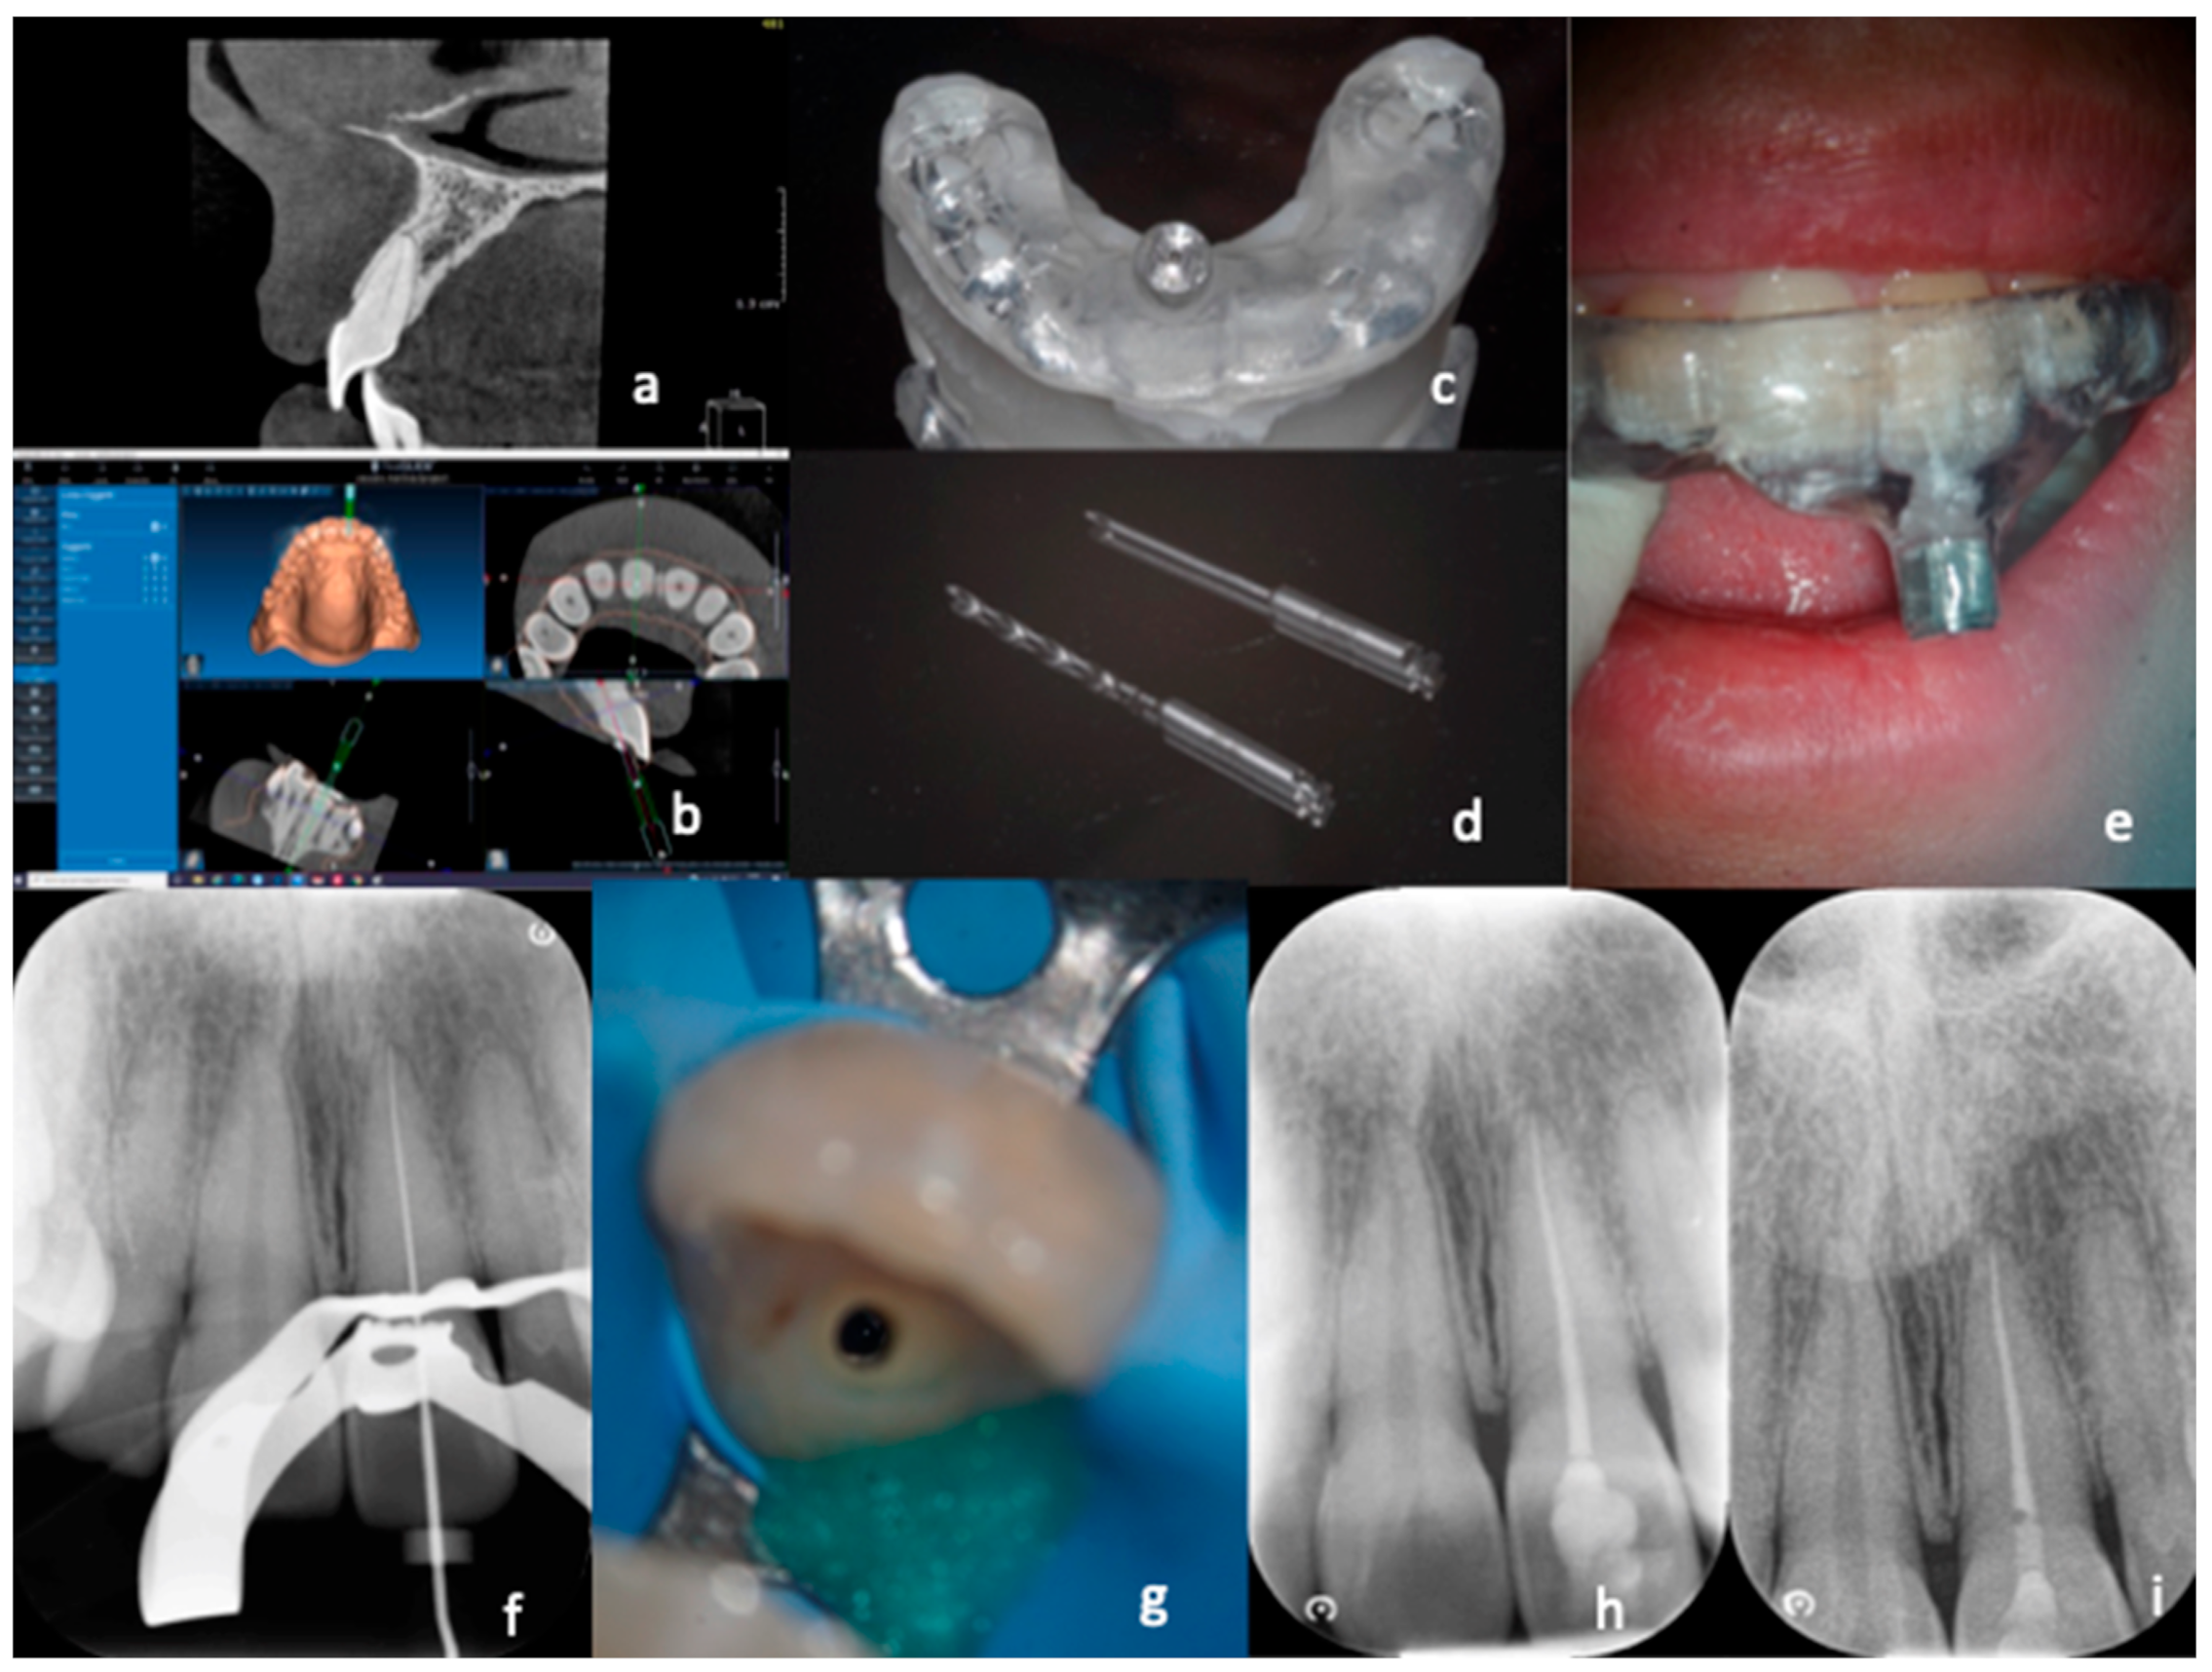

Figure 1. Treatment with “optimal precision” of a calcified canal. After carrying out a small FOV CBCT (a), which highlights the calcification of the canal, the DICOM data of the CBCT are coupled with the STL data derived from the digital impression (b). The result is a digital project that enables creation of a guide (c) which allows insertion of the two drills with a diameter of 0.9 mm up to the desired depth to reach the canal (d). The guide is inserted (e) and proceeds, with short excursion movements, to reach the canal. After rubber dam application, the working length is determined (f). Dentin removal is reduced even in the most coronal segment (g). Photos from the end of the treatment revealed correct obturation of the root canal system (h). A control X-ray was taken after six months (i).

During the appointment with the patient (Figure 1), the correct positioning and the stability of the template were tested, checking the tightness and the proper insertion thanks to the small windows opened in the occlusal part. None of the cases required template correction. At this point, local anesthesia was performed using articaine 1:100,000, and the template was inserted with no rubber dam in order to promote stability. A pencil tip was inserted into the sleeve (0.70 or 0.90 mm in diameter, depending on the size of the chosen bur), and the penetration point of the bur was marked on the enamel. The enamel was then removed with a round diamond bur mounted on a red handpiece until the dentin was reached. The template was removed, and the canal was washed with saline solution to cool down the tooth and remove debris. Again, the guide was positioned, and the dentin was removed, inserting the bur 2–3 mm using a blue handpiece at 10,000 rpm. Each maneuver was followed by removing the guide, washing with physiological solution, and checking the cavity with the operating microscope. Every three steps, the bur was removed from the handpiece and inserted into the canal to ensure its correct orientation. The guide was removed when the bur reached the maximum depth required to access the patent canal. After washing with physiological solution, a stainless-steel endodontic instrument was inserted (C+ File Ø 10, Dentsply Maillefer, Ballaigues, Switzerland CH), attempting to penetrate the canal. If this occurred, the canal was irrigated with 5.25% sodium hypochlorite after rubber dam isolation. Afterward, scouting of the canal was performed using a C+ File Ø 06 (Dentsply Maillefer, Ballaigues, Switzerland CH), connected with the apex locator (Root ZX, J. Morita Corporation, Tokyo, Japan), until WL was reached. The WL was immediately confirmed with a peri-apical X-ray. Coronal enlargement was carried out first with Scout RaCe (sizes 10, 15, and 20; taper 0.02) and then with Race series (sizes 20, 25, and 30; taper 0.04) instruments (FKG dentaire, La Chaux du Fonds, CH), while if the foramen was larger than 30, greater-diameter instruments were chosen. Each instrument insertion was followed by a wash with 1 cc of 5.25% sodium hypochlorite. After final cleansing with 5.25% sodium hypochlorite and 17% EDTA, the canal was rinsed with physiological solution, dried with absorbent paper cones, and sealed with bioceramic cement sealer (Bioroot RCS, Septodont, Saint Maur des Fosses, France) by using the single cone technique.